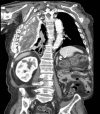

Empyema necessitans is a rare clinical finding nowadays. We report the case of a patient admitted in our ward for investigation of an unknown onset anterior chest wall mass, with no accompanying signs or symptoms. It is noteworthy that the patient had had pulmonary tuberculosis submitted to thoracoplasty more than 60 years before. Thoracic MRI showed a large heterogeneous mass, with a thick wall and internal septations located at the right anterior chest wall, as well as a heterogeneous content inside the right pleural cavity, with direct communication between both. An aspirative puncture of both masses was performed, with positive cultures for Mycobacterium tuberculosis, thus leading to the diagnosis of pleural tuberculosis with anterior chest wall empyema necessitans. A drain was inserted and antibiotics started. This case draws our attention to a very rare complication of pulmonary tuberculosis and its surgical treatment, though it aroused many decades after primary infection.